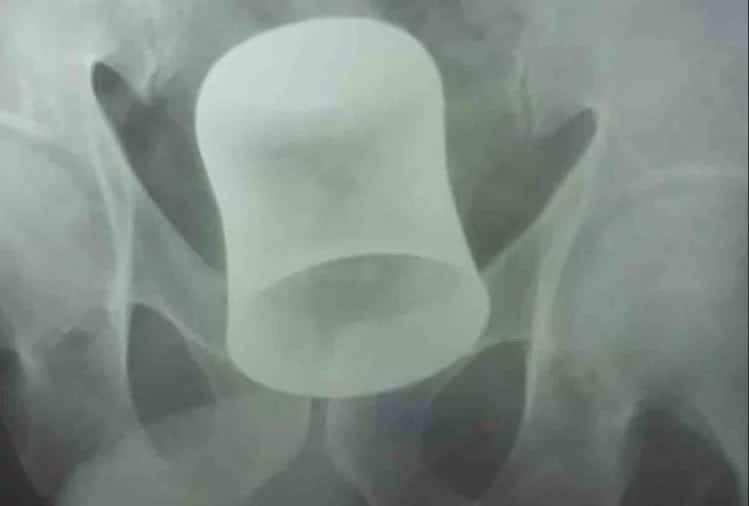

कानपुर: कानपुर में एक हैरान कर देने वाला मामला सामने आया जब एक बुजुर्ग के प्राइवेट पार्ट से स्टील का ग्लास उनके पेट तक जा पंहुचा. जिसकी वजह से बुजुर्ग की तबियत बिगड़ गयी, परिजनों ने उन्हें रामा हास्पिटल एंड रिसर्च सेंटर में एडमिट कराया. जब बुजुर्ग का अल्ट्रासाउंड कराया गया तो स्टील का ग्लास कमर के उपरी हिस्से पर फंसा हुआ दिखा. डॉक्टरों की टीम ने ढाई घंटे के ऑपरेशन के बाद बुजुर्ग के पेट से ग्लास बाहर निकाला.

रामा हास्पिटल एंड रिसर्च सेंटर हास्पिटल के सर्जन डॉ दिनेश कुमार के मुताबिक पेशेंट के गुदा द्वार से होते हुए स्टील का ग्लास पेट तक पहुंच गया था. पेशेंट के ऑपरेशन में लगभग ढाई घंटे का वक्त लगा था ,जिसमे पेट में चीरा लगाकर ग्लास को बाहर निकाला गया है. अब पेशेंट पूरी तरह से स्वस्थ्य है और उनकी अस्पताल से छुट्टी कर दी गयी है.

उन्होंने बताया कि पेशेंट के प्राइवेट पार्ट से ग्लास निकालने का प्रयास किया गया. लेकिन जब इसमें सफलता नहीं मिली तो इसके बाद इनके ऑपरेशन करने की योजना बनाई गई.टॉप हेडलाइंस